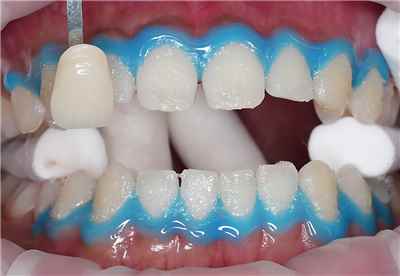

치아 변색 외부 요인